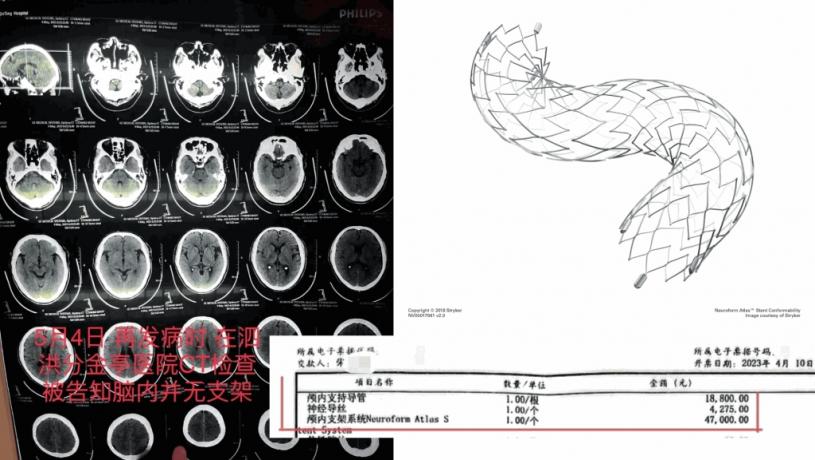

當時醫生告知家屬,如果不予血管內介入治療,患者隨時可能因動脈閉塞導致死亡。經家屬簽字同意,4月6日,齊某再次作為主刀醫生,對朱老翁進行經皮基底動脈支架植入術,術後告知家屬手術成功。手術記錄均顯示,朱老翁安裝了一枚進口Neuroform Atlas 4.5/21支架,病程記錄也多次提到「血管狹窄明顯改善」。朱老翁4月10日「康復」出院,家屬結清了住院醫療費用,合計12萬餘元,部分自費。收據顯示,其中顱內支持導管收費1.88萬,神經導絲4275元,而Neuroform Atlas進口顱內支架為4.7萬元。

到了5月4日,朱老翁突發嚴重腦梗,被救護車送至江蘇省宿遷市泗洪縣分金亭醫院搶救,CT檢查竟發現其顱內段部分動脈已嚴重堵閉,同時未有植入支架。朱先生無法接受,以為是小醫院檢查不出來,決定轉回宿遷市第一人民醫院,此時主刀醫生齊某才承認,之前植入支架失敗。